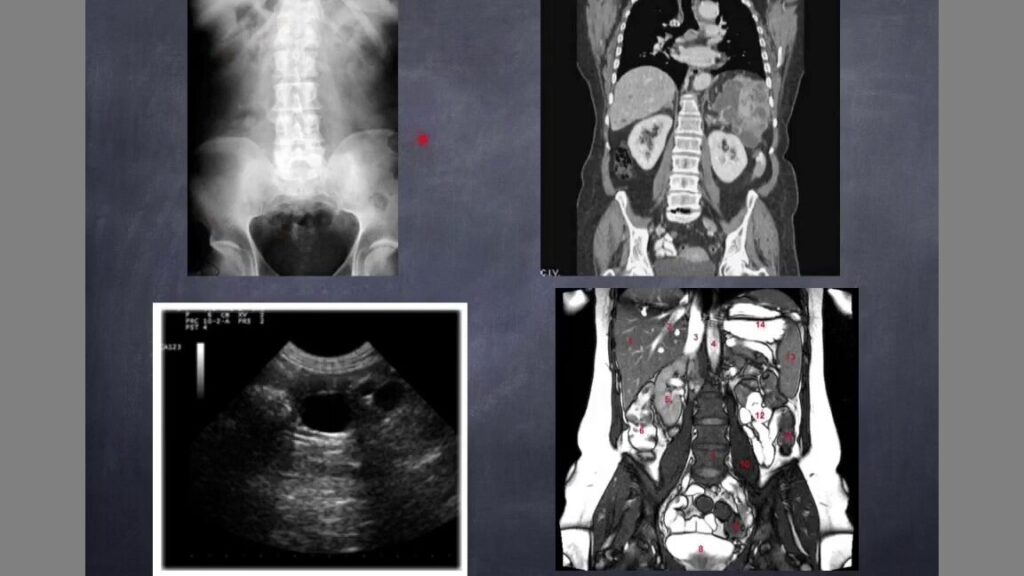

La ecografía o ultrasonido es una técnica que utiliza ondas sonoras de alta frecuencia para crear imágenes del interior del cuerpo. El equipo consta principalmente de un transductor que emite estas ondas y recibe los ecos que rebotan en los tejidos. Estos ecos se transforman en imágenes visibles en tiempo real en un monitor.

Este método es no invasivo, seguro y indoloro, ya que no utiliza radiación ni requiere incisiones. A diferencia de técnicas como los rayos X o la resonancia magnética, la ecografía no expone al paciente a radiación ionizante, lo que la hace especialmente adecuada para embarazadas y niños.

Aplicaciones médicas más comunes de la ecografía o ultrasonido

La ecografía se emplea en múltiples áreas de la medicina debido a su versatilidad. Entre sus aplicaciones más frecuentes destacan:

- Diagnóstico en órganos internos hígado, riñones, tiroides, corazón y otros órganos pueden evaluarse para detectar anomalías o enfermedades.